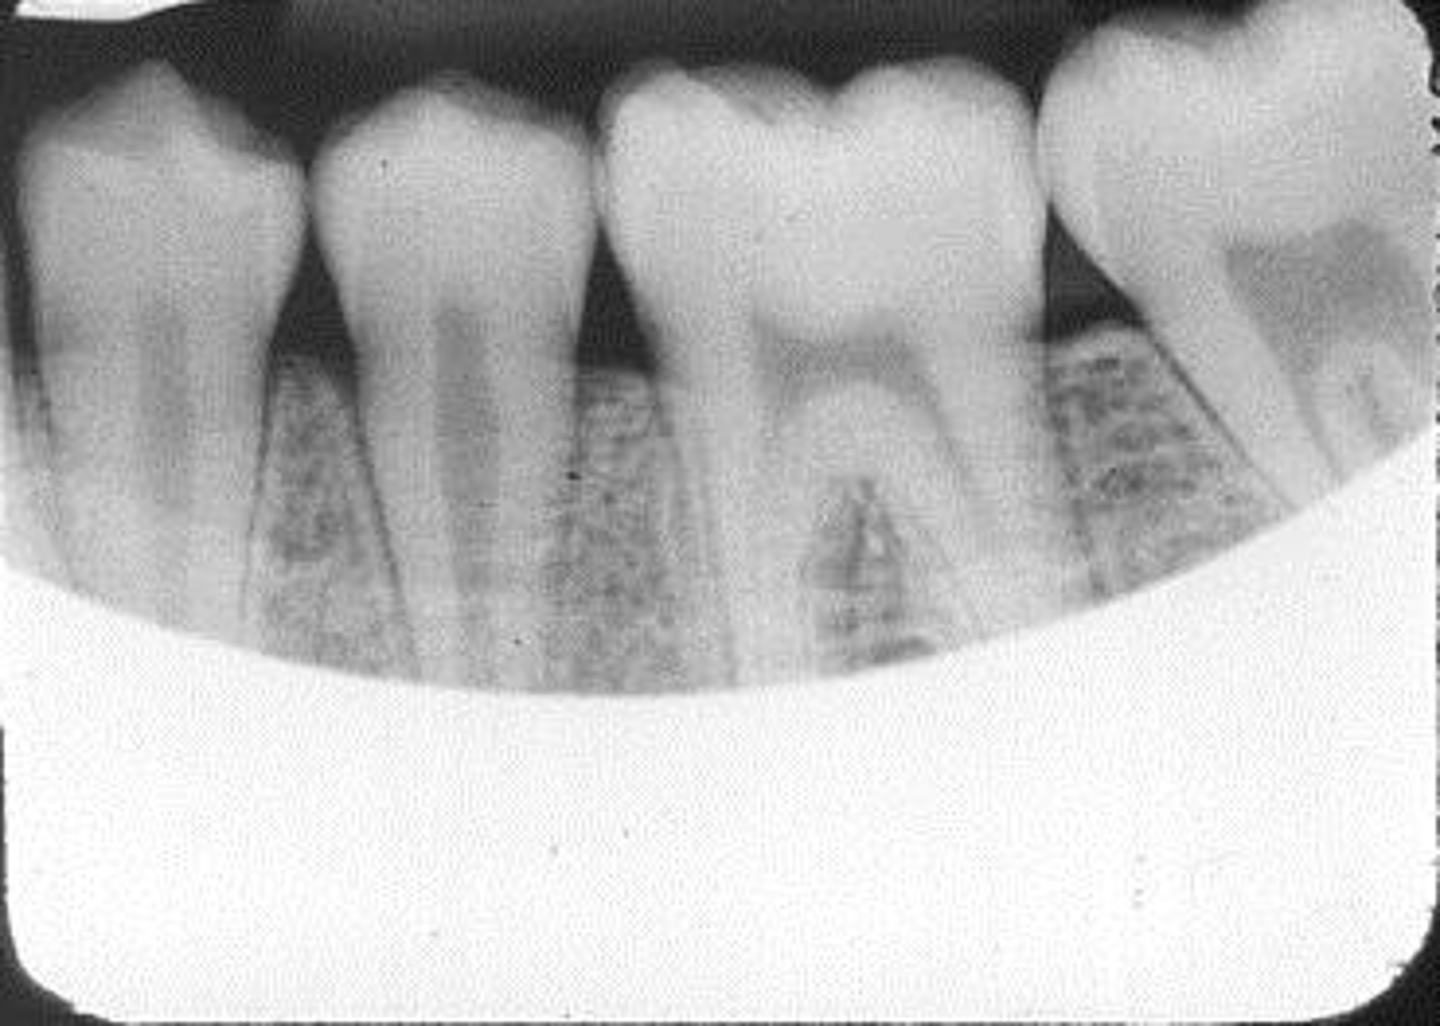

Wrong film direction, backwards, positive angulation, wrong film size, no open contacts

What is this error?